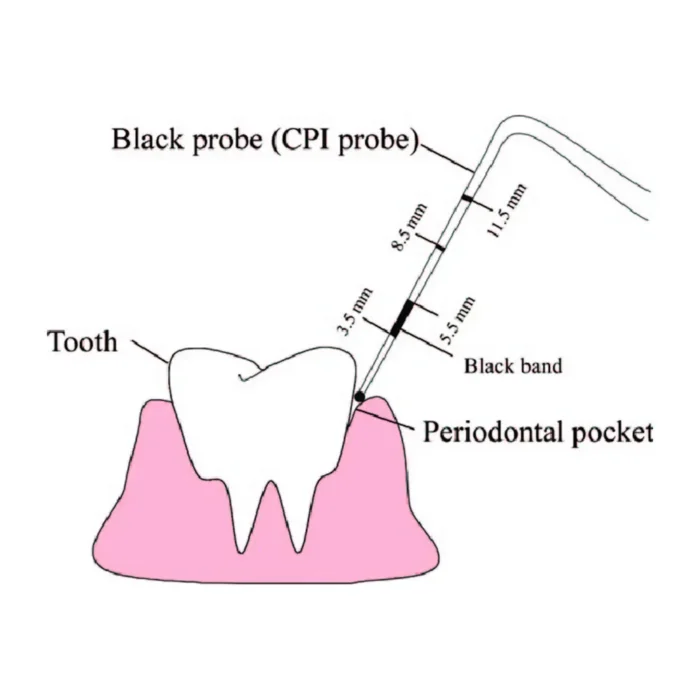

- Screening probe (PCP15/11.5): The second end of the probe is specifically designed for a periodontal screening and measuring pocket depths. It has a diameter of 1.5 millimeters and is marked with increments (11.5) to measure the depth of periodontal pockets accurately.

- Accurate measurements: The probe is marked with clear millimeter increments, facilitating precise measurements of pocket depths. This helps in tracking changes in gum health over time and planning appropriate treatment interventions.

GDC Double End Probes Unc 15 / Screening Probe #1 (PCP15/11.5) is a dental instrument used by dentists and dental hygienists for periodontal probing and screening. It consists of a double-ended design with different measurements on each end. The “Unc 15” marking refers to the first end of the probe.UNC15 Probe has markings mm1-2-3-4-5-6-7-8-9-10-11-12-13-14-15 and Screening Probe has markings mm 3.5-5.5-8.5-11.5 inscribed onto the head of these instruments for accuracy and readability.

The second end of the probe is labeled as “Screening Probe #1” or “PCP15/11.5.” This end is specifically designed for periodontal screening and measuring pocket depths. “PCP” stands for “Periodontal Community Probe,” and the number “15” indicates the working end’s diameter, which is 1.5 millimeters. The “11.5” represents the marking increments on the probe, indicating the millimeter markings from the tip of the probe to its base. These markings help measure the depth of periodontal pockets, which can be an indicator of gum disease or other oral health conditions.